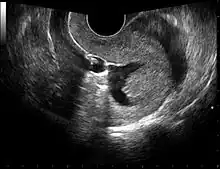

The examination can be performed by transabdominal ultrasonography, generally with a full bladder which acts as an acoustic window to achieve better visualization of pelvis organs, or by transvaginal ultrasonography with a specifically designed vaginal transducer. Transvaginal imaging utilizes a higher frequency imaging, which gives better resolution of the ovaries, uterus and endometrium (the fallopian tubes are generally not seen unless distended), but is limited to depth of image penetration, whereas larger lesions reaching into the abdomen are better seen transabdominally. Having a full bladder for the transabdominal portion of the exam is helpful because sound travels through fluid with less attenuation to better visualize the uterus and ovaries which lies posteriorly to the bladder. The procedure is by definition invasive when performed transvaginally. Scans are performed by health care professionals called sonographers, or gynecologists trained in ultrasound.

Through transvaginal sonography ovarian cysts can be aspirated. This technique is also used in transvaginal oocyte retrieval to obtain human eggs (oocytes) through sonographic directed transvaginal puncture of ovarian follicles in IVF.

Sonohysterography